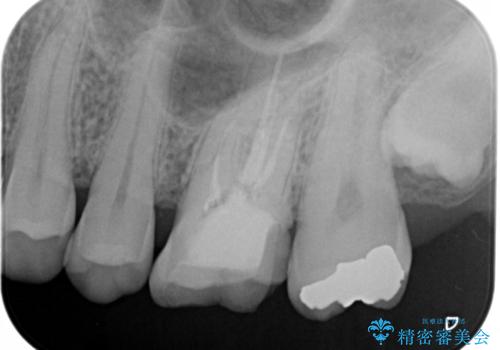

- 左上7番の銀歯をセラミックにやり変え希望の患者様です。

切削量・形態からセラミックインレーでの治療を計画しました。

銀歯とその直下のう蝕を除去した後、CRにて裏層しています。

インレー装着の際はラバーダムを使用しています。